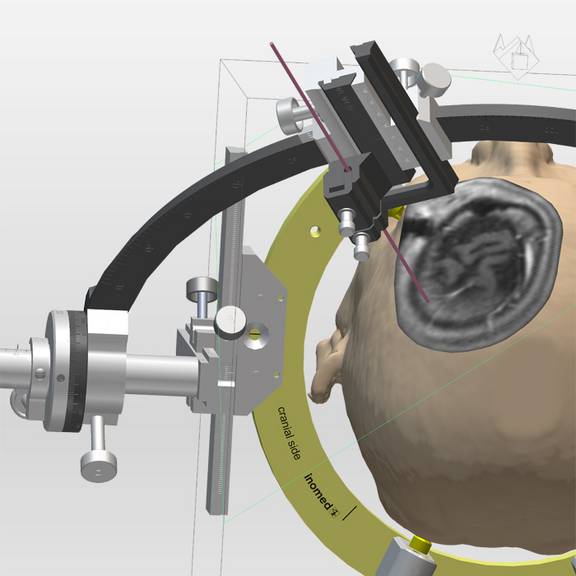

Die Möglichkeit einer schnellen Generierung von 3D Ansichten des Patientenschädels hilft bei der Verifikation der Zielpunktplanung im Zuge der THS. Durch Projektion des verwendeten Stereotaxie-Systems bekommt der Anwender eine realistische Darstellung über Anordnung und Auswirkung der Trajektorie-Planung auf den Systemaufbau.

Das Generieren von Volumen gestattet die Visualisierung von Strukturen, deren Bedeutung für die Zielpunktverifikation bei der THS groß ist. Ob nun Bild für Bild die gewünschte Struktur markiert oder per Softwarefunktion anhand von Schwellwerten automatisch erkannt wird, schlussendlich kann jedes Volumina als Objekt in der 3D-Visualisierung dargestellt werden.

Viele weitere Funktionen vervollständigen das iPS, wie das Messen von Distanzen, Winkeln und Flächen. Für die Verifikation der Trajektorie können die Bilder auf alle typischen Schnittebenen (Sagittal, Coronal, Axial) ausgerichtet werden und zusätzlich entsprechend der Draufsicht der Trajektorie (Perpendicular oder Probe´s eye) oder entlang der Trajektorie eingestellt werden.